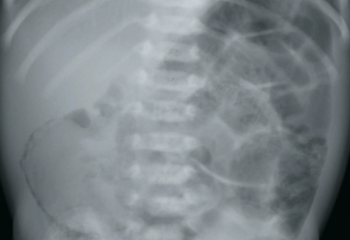

A 6-day-old, late-preterm male neonate presents to his pediatrician’s office with bilious emesis and is admitted for further evaluation. He was born at 36 weeks and 6 days via spontaneous vaginal delivery to a 23-year-old G4P4 mother with negative serologies, negative antenatal Group B Streptococcus testing, and no significant prenatal events. His stay in the newborn nursery was unremarkable. The neonate is exclusively breastfed, has no history of rectal bleeding, and passed meconium within the first 24 hours.